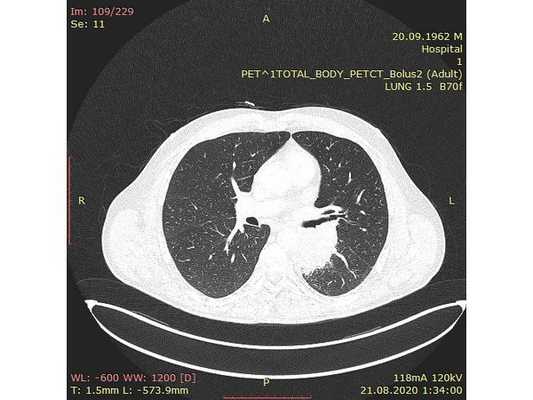

Анамнез заболевания: на фоне 40-летнего стажа курения (по 1 пачке в день) и хронической обструктивной болезни легких (ХОБЛ) в ноябре 2007 г. у больного появилась боль в грудной клетке справа. При обследовании в поликлинике по месту жительства по данным рентгенографии и КТ органов грудной клетки выявлено узловое образование в верхней доле левого легкого. Обследован в ЦНИИ туберкулеза РАМН. После 2-месячного противотуберкулезного лечения рентгенологической динамики не отмечено. Заподозрен рак легкого. Направлен к онкологу. Обратился в МНИОИ им. П.А. Герцена. При обследовании в институте по данным КТ органов грудной клетки в апреле 2008 г. выявлено опухолевое образование в верхней доле левого легкого, а также в верхней доле правого легкого, трактуемое как первично-множественный синхронный рак легких (рис. 1). Рис. 1. Компьютерные томограммы органов грудной клетки. а, б — объяснение в тексте. Диагноз верифицирован морфологически посредством последовательных трансторакальных пункций образований под контролем КТ и УЗИ. Цитологическое исследование: плоскоклеточный ороговевающий рак (слева); низкодифференцированный плоскоклеточный рак (справа).

При КТ органов грудной клетки (26.02.08) обнаружены периферическое солидное узловое образование верхней доли левого легкого с неровными бугристыми контурами размером 1,5×1,7 см (рис. 1, а) и частично солидное периферическое узловое образование в верхушечном сегменте правого легкого со спикулообразными контурами размером 1,2×1,0 см (см. рис. 1, б). Трахея и бронхи (1—3-го порядка) проходимы, не деформированы. Жидкости в плевральных полостях не выявлено. Средостение структурное. Внутригрудные лимфатические узлы не изменены. Мягкие ткани и костные структуры грудной клетки без изменений.